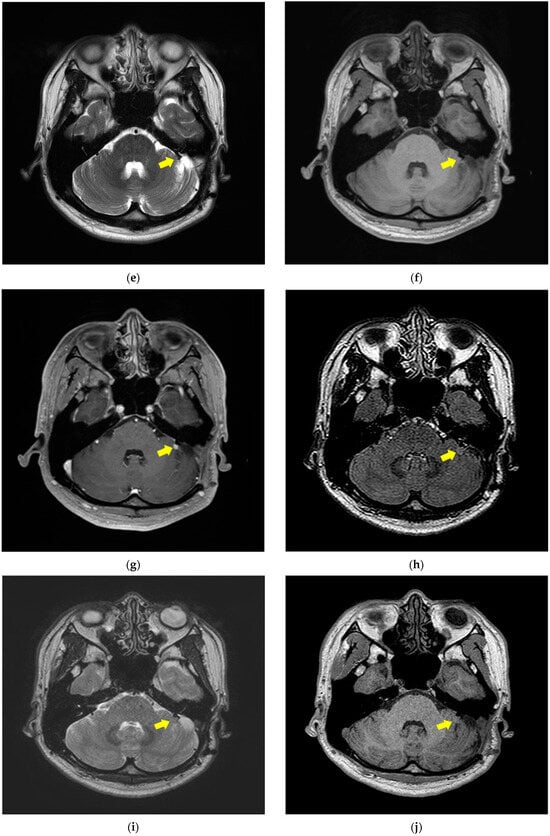

2.1. MRI Dataset

3.1. Image Pre-Processing